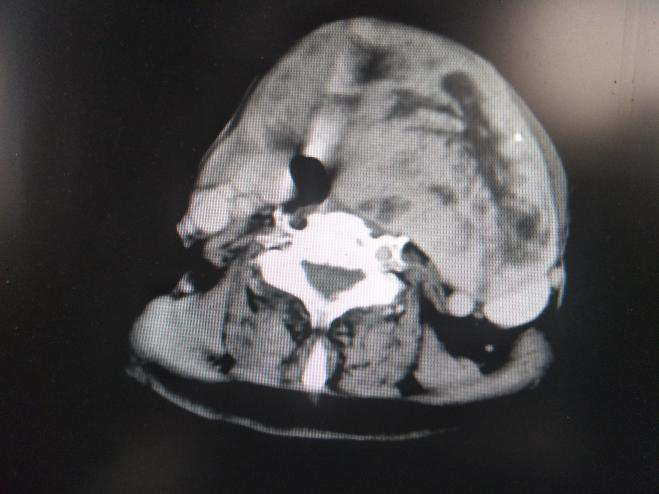

由于实在是受不了疾病的困扰,本着试试看的态度,她在家人的陪同下乘车从道县来到了永州市中心医院北院,经门诊收入头颈肿瘤乳腺外科住院治疗。入院后科室卿伯华主任医师、段群欢主任医师组织科室人员进行了病例讨论,考虑到患者有脑梗死病史及气管严重移位可能出现的插管困难,遂积极请神经内科及麻醉科等相关科室会诊,完善相关检查,在相对安全的情况下于2017年10月23日在全身麻醉+气管插管下为患者行了甲状腺巨大肿瘤切除术,术中见瘤体表面的血管都有食指般粗细,经过仔细的分离结扎,完整的切除了肿块,保留了颈部的重要血管、神经、肌肉,肿瘤切除后患者气管、食管恢复到了正常解剖位置。手术用时短,术中出血量极少,患者生命体征稳定,术毕麻醉苏醒后安返病房。